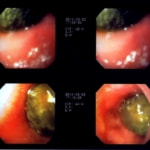

症例:炎症性ポリープ M.ダックス 10歳 オス

主訴:8ヶ月前から便が細くなり、血が混じることがある。その他、元気・食欲等、一般状態は良好。

経過:超音波検査にて直腸壁の肥厚(5㎜)が認められた。また、直腸検査で直腸全周に結節状病変を触知し、出血も確認された。消炎剤、抗生剤、整腸剤による治療への反応が長期的に悪いため、生検も含めた内視鏡検査を実施した。

内視鏡検査:肛門付近の直腸全周に、炎症および出血を伴う結節状病変を多数認めた。

病理検査:直腸の病変は、良性の非腫瘍性病変の一つである“炎症性ポリープ”と診断された。

診断後経過:炎症性ポリープは多発する傾向や腫瘍に転化する可能性があるため、消炎剤、抗生剤、整腸剤による内科療法を継続しながら、現在プルスルー法による外科的摘出術を検討中。

◎炎症性ポリープとは

近年、ミニチュアダックスで好発が知られている良性の腫瘍性の病変です。しばしば多発し、また腫瘍に転化する事があります。